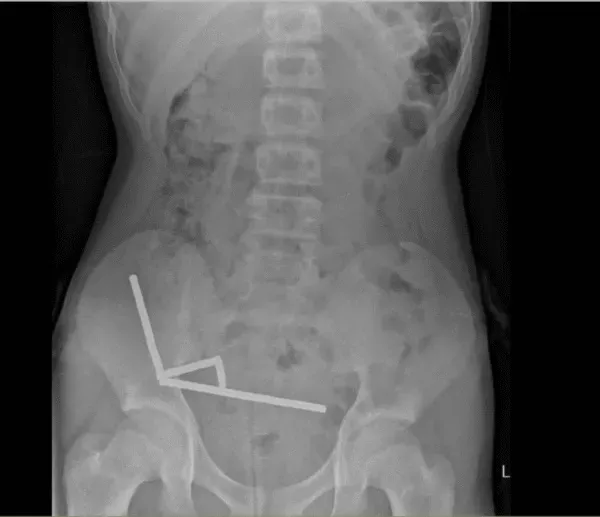

医生通过 X 光片观察到,男孩肠道的不同部位出现了四条线状的磁铁链。

腹部 X 光片显示了磁铁分布情况 来源:Lekamalage et al.,?NZMJ, 2025